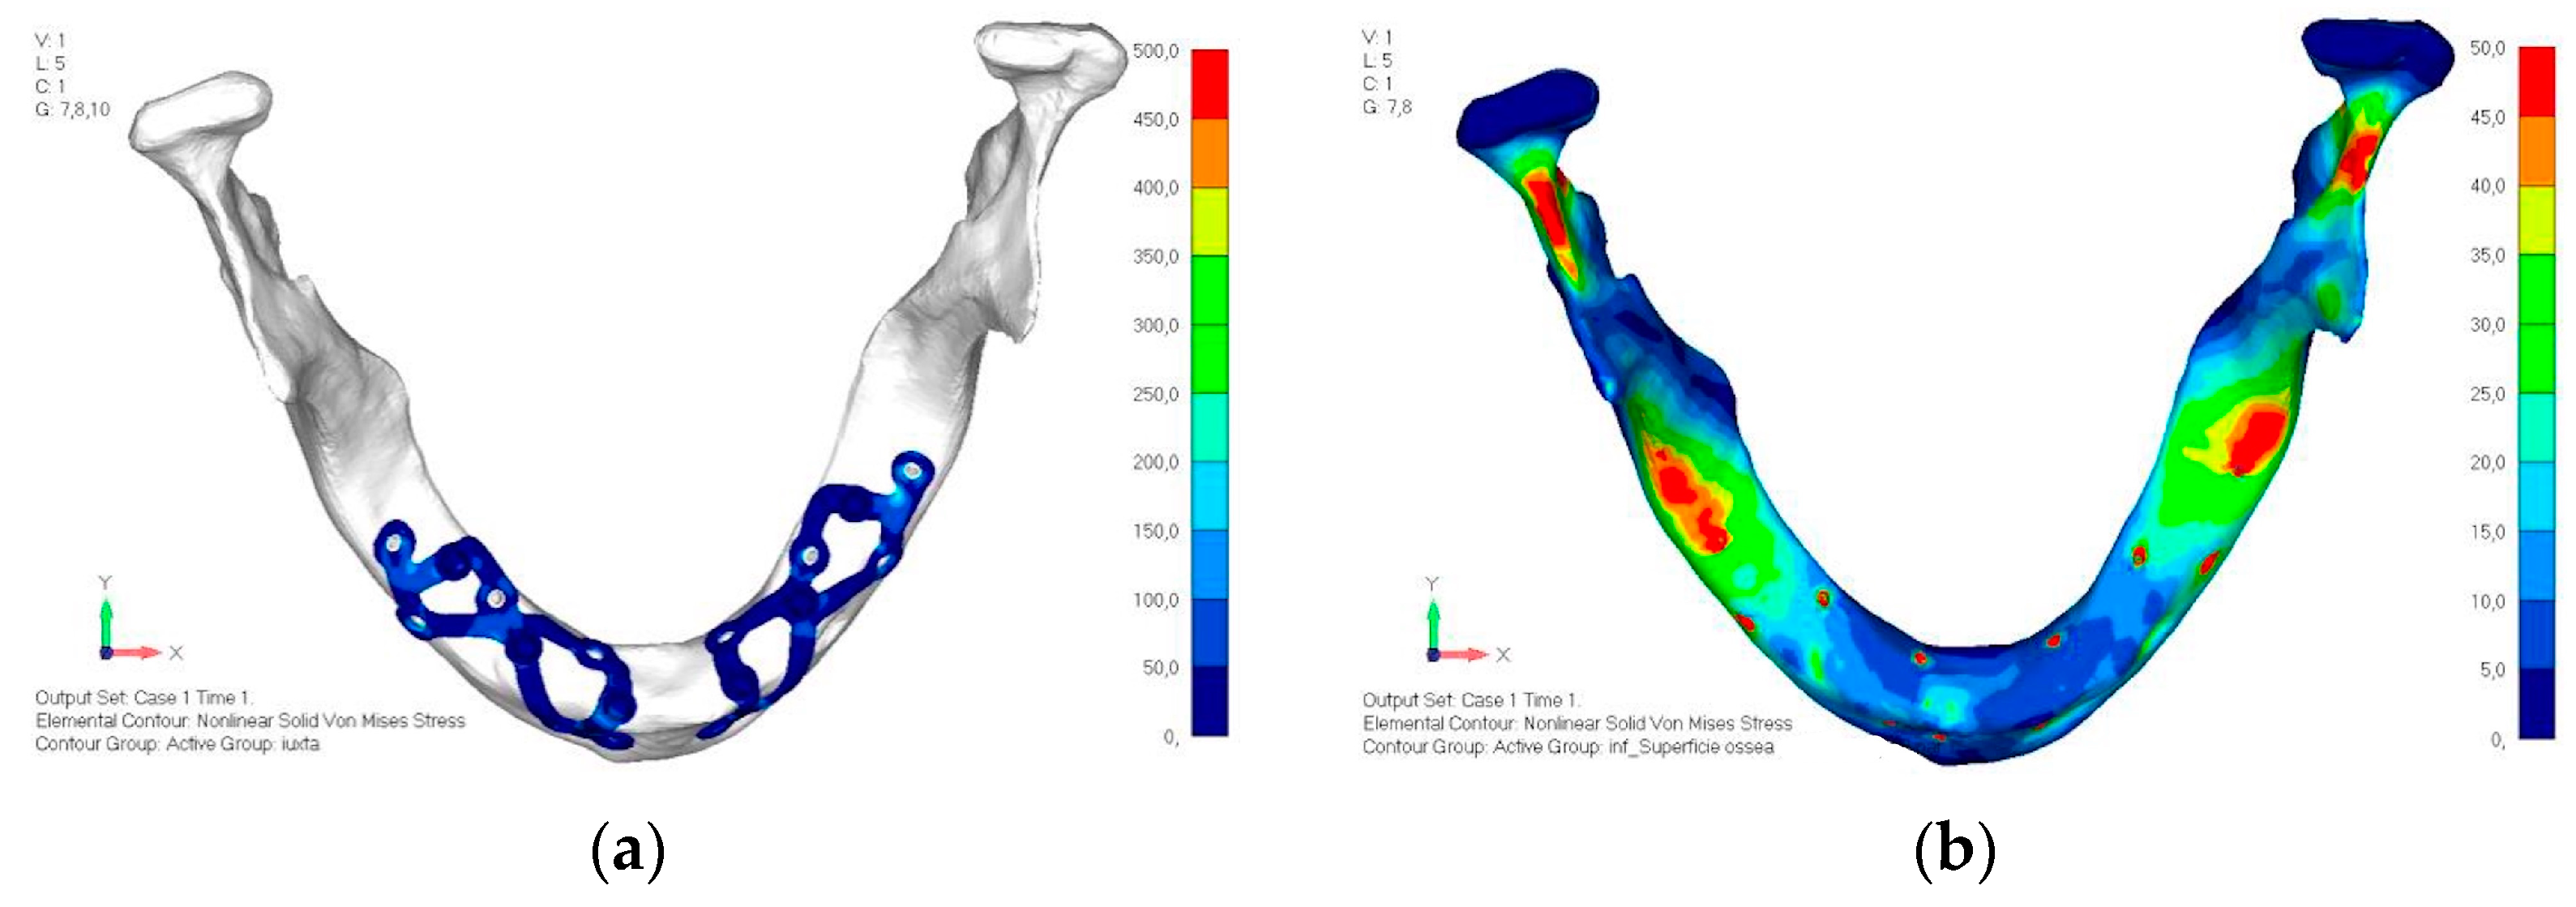

- Model V0. This model represents the initial analysis performed on the lower arch. The implant consists of two completely separate hemi-arches. The situation observed in the lower model is very similar to that found in the upper model. The most significant load is load 3 (Figure 20a,b), corresponding to chewing in the anterior right sector. Loads distributed over larger areas, such as configurations 1 and 2, result in less stress on both the implant and the bone (Figure 21 and Figure 22).

- Even in the lower model, the stresses observed in the peri-implant bone are always acceptable and significantly lower compared to those found in the upper implant. In the worst case, peak stresses reached 250 MPa, which ensures an adequate safety margin. From the bone perspective, in load configuration 3, it is noted that stresses exceed 50 MPa even in areas distant from the implant, such as near the condyles and in the posterior alveolar process.